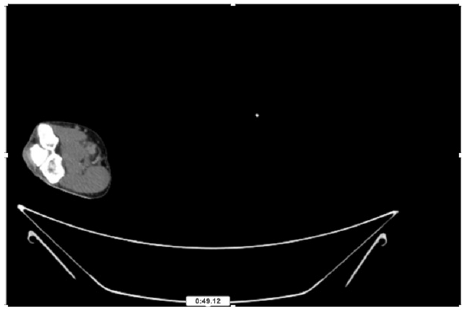

55-years-old chronic smoker had acute, severe pain in the right upper limb for one week; it was cold upto mid arm with skin discoloration. He also noticed numbness and weakness of movement of elbow joint. He underwent below elbow amputation in February 2023 for acute ischemia of left upper limb. He was a current chronic smoker; 15 pack year. General condition was weak; temperature was normal; blood pressure was 100/60mmHg; heart rate was 92/minutes with sinus rhythm; SpO2 was 97% on air; heart was normal. In lower extremities, all peripheral pulses were intact. Local Examination of right upper limb revealed as follows: tenderness; coldness; discoloration; decreased motor function and sensory modalities. Axillary, brachial and radial pulses were not palpable. Hand-held Doppler failed to detect any signal in arterial system; therefore, we arranged for emergency embolectomy. complete occlusion of right upper limb arterial system Full blood count showed high hemoglobin (14.6gm%); normal total WBC and platelet count. Coagulation profile was normal. Parenteral unfractionated heparin, antibiotics, tramadol, proton-pump inhibitors, anti-platelets and HMG CoA reductase inhibitors were given. Doppler ultrasound demonstrated complete occlusion of right upper limb arterial system. CT Angiogram illustrated occlusion of subclavian artery downwards on both sides. Figures 1-14 shows complete occlusion of right subclavian artery without collaterals. On Day ‘2’ of admission, the patient passed black tarry stool for 3 times. However, the vital signs were stable; blood pressure was 100/60mmHg; heart rate was 92/min; SpO2 was 97% on air; the abdomen was soft and not tender. Above elbow amputation was done on Day ‘2’ of admission. Intra-operative findings were as follows: (1) no active bleeding at brachial artery; (2) thrombosis along brachial artery; (3) muscle color and consistency were not healthy.

Figure 10: CT Angiogram at upper arm showing totally occluded right axillary artery; normal internal carotid artery and external carotid artery.